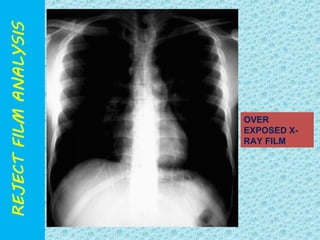

OVER

EXPOSED X-RAY

FILM